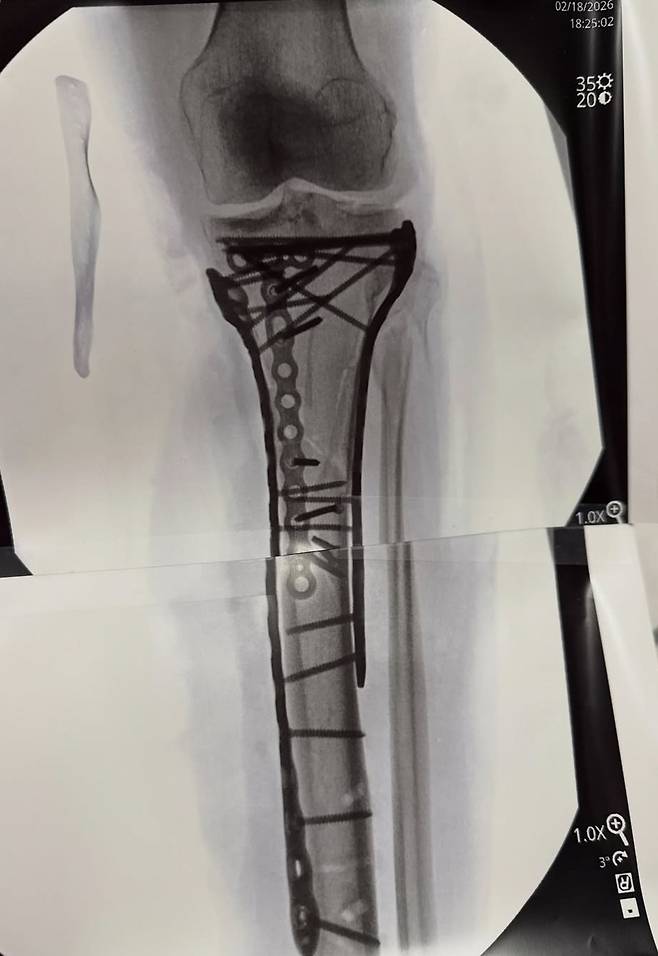

그는 금속판과 나사가 박힌 엑스레이 사진도 공개했다. 본은 올림픽에서 총 3개의 메달을 따냈다. 2010년 밴쿠버 대회에서 활강 금메달, 슈퍼대회전에서 동메달, 2018년 평창 대회에선 활강 동메달을 목에 걸었다. 2014년 소치 대회는 부상으로 불참했다.